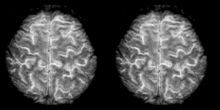

Functional magnetic resonance imaging (fMRI) has intriguing implications for the study of memory in humans, however it can also be used in animal models. fMRI can be used to assess brain functionality in monkeys in the context of a variety of behavioral tasks.[26] Structural MRI can be used to examine the extent and location of brain lesions, so that behavioral abnormalities observed can be directly linked to specific brain structures.[27] High-resolution fMRI can help locate and assess the functionality of large neural networks so that these regions can be further studied using more traditional electrophysiological recording devices.[26]